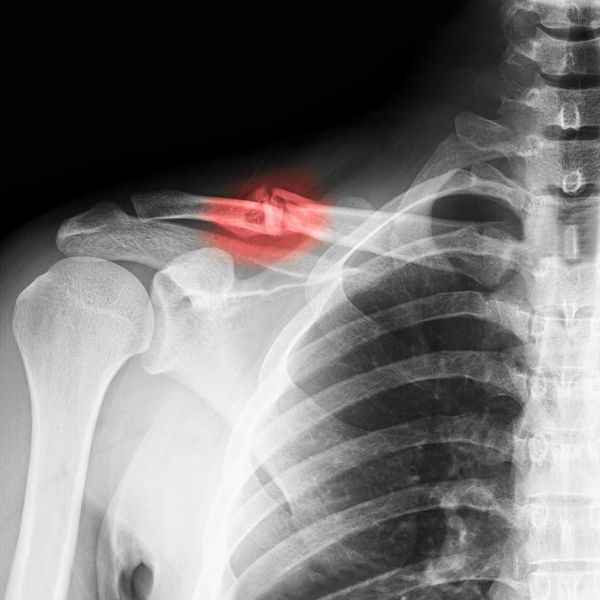

Red Light Therapy for Bone Recovery

In the realm of regenerative medicine, a fascinating and increasingly popular therapy is shedding new light on how our bodies heal – quite literally. Red light therapy, also known as photobiomodulation (PBM) or low-level laser therapy (LLLT), is emerging as a powerful, non-invasive tool to accelerate bone repair and improve skeletal health.

Both in vivo (within a living organism) and in vitro (in a laboratory setting) studies have consistently highlighted the positive impact of red light therapy on bone healing. Its ability to accelerate the repair of fractures and bone defects has made it a subject of increasing interest in orthopaedic practices.